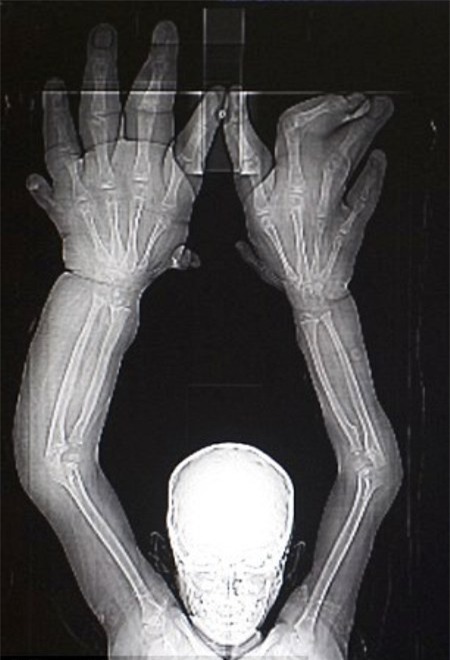

Theo tờ Mirror đưa tin, Kaleem đến từ Ấn Độ mắc phải dị tật hiếm gặp từ khi mới sinh khiến đôi bàn tay cậu bé to gấp đôi những đứa trẻ sơ sinh khác. Được biết, đây là căn bệnh Macrodactyly - phình đại ngón hay còn biết đến với tên gọi khác là dị tật bẩm sinh ở chi. Nguyên nhân gây ra chủ yếu do gene duy truyền, ốm đau trong thời kỳ thai nghén, do dùng thuốc, do nhiễm độc (dioxin…), nhưng đa số các trường hợp thì nguyên nhân không rõ ràng. Hiện nay trên thế giới tỷ lệ trẻ sơ sinh gặp phải trường hợp này là 1/500.

Càng lớn, đôi bàn tay cậu bé cũng phát triển theo và dẫn trở nên mất cân đối với trọng lượng cơ thể. Tới nay, khi em được 8 tuổi thì mỗi bên bàn tay đã nặng tới 8 kg và dài 33 cm tính từ cổ tay đến cuối ngón tay giữa .